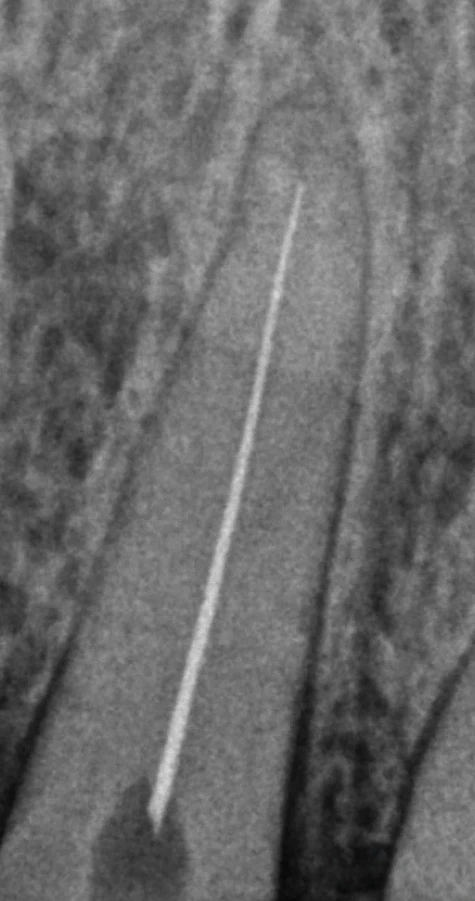

Leczenie kanałowe z użyciem lasera

Zabieg przeprowadzamy pod mikroskopem, z użyciem koferdamu (specjalnej osłony izolującej ząb) i nowoczesnych narzędzi maszynowych. W miarę możliwości kończymy leczenie podczas jednej wizyty.